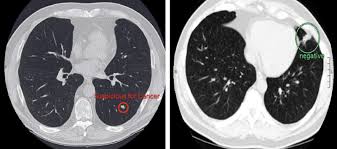

Each has its own strengths. A ct scan can show whether breast cancer has spread to the lungs or liver. The lung cancer detection is the extension of the image processing that produces the results of feature extraction and feature selection after segmentation. Breast cancer type and stage: The image shows your bones, organs, and soft tissues more clearly. Monitor the effectiveness of certain. Ct scans and cat scans describe the same imaging test. A radiographer operates the scanner. You can have a ct scan done at the radiology or radiation oncology center of a hospital. This provides a series of images from many different angles. Medically reviewed by seunggu han, m.d. It's also important to follow recommended screening guidelines, which can help detect certain cancers early. If you have a condition like cancer, heart disease.

The whole appointment can take up to an hour and a half depending on which part of your body they are scanning. The risks for younger adults and especially children are. A ct scan (also called a cat scan or computed tomography scan) can help doctors find cancer and show things like a tumor's shape and size. What is nci doing to improve ct imaging? Knowing this helps you and your doctor choose the best treatment options.

Where can people get more information about ct? What does a ct scan show? Definition purpose description preparation aftercare risks normal results. These techniques include ct scans, mri scans and radioisotope scans. Learn more about cat scans today. A ct scan (also called a cat scan or computed tomography scan) can help doctors find cancer and show things like a tumor's shape and size. Medically reviewed by seunggu han, m.d. Diagnose and assess breast tumors. Detection of cancer prior to onset of symptoms (via several tests/imaging). A ct scan is one of the most frequently utilized exams to detect cancer and to show things such as a tumor's shape and size. It does a better job of identifying a small mass in a woman's. The whole appointment can take up to an hour and a half depending on which part of your body they are scanning. What is nci doing to improve ct imaging?